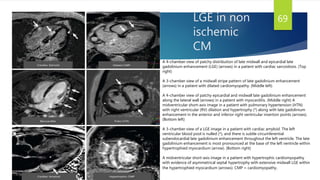

LGE in non

ischemic

CM

69

A 4-chamber view of patchy distribution of late midwall and epicardial late

gadolinium enhancement (LGE) (arrows) in a patient with cardiac sarcoidosis. (Top

right)

A 3-chamber view of a midwall stripe pattern of late gadolinium enhancement

(arrows) in a patient with dilated cardiomyopathy. (Middle left)

A 4-chamber view of patchy epicardial and midwall late gadolinium enhancement

along the lateral wall (arrows) in a patient with myocarditis. (Middle right) A

midventricular short-axis image in a patient with pulmonary hypertension (HTN)

with right ventricular (RV) dilation and hypertrophy (*) along with late gadolinium

enhancement in the anterior and inferior right ventricular insertion points (arrows).

(Bottom left)

A 3-chamber view of a LGE image in a patient with cardiac amyloid. The left

ventricular blood pool is nulled (*), and there is subtle circumferential

subendocardial late gadolinium enhancement throughout the left ventricle. The late

gadolinium enhancement is most pronounced at the base of the left ventricle within

hypertrophied myocardium (arrow). (Bottom right)

A midventricular short-axis image in a patient with hypertrophic cardiomyopathy

with evidence of asymmetrical septal hypertrophy with extensive midwall LGE within

the hypertrophied myocardium (arrows). CMP = cardiomyopathy.

70